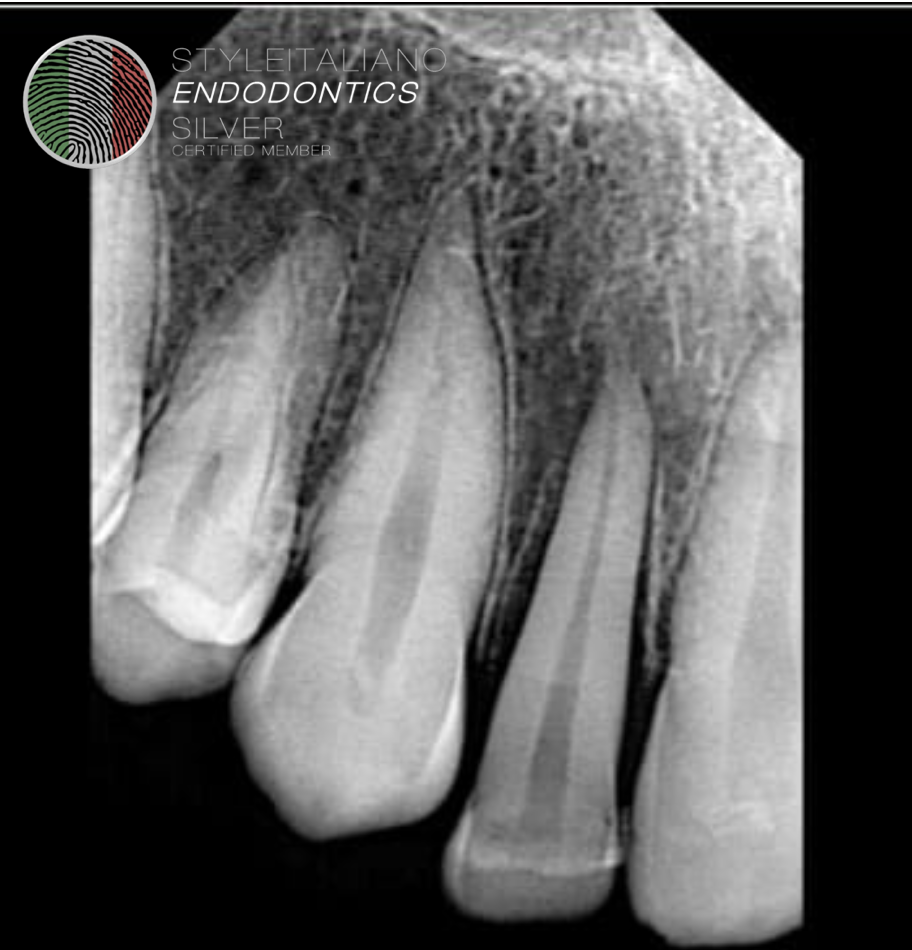

Fig. 1

Pre op radiograph showing fractured right lateral incisor.